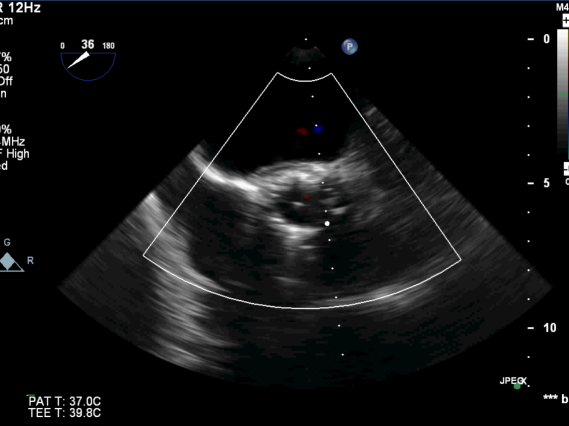

图1. 主动脉瓣钙化明显,并中量反流